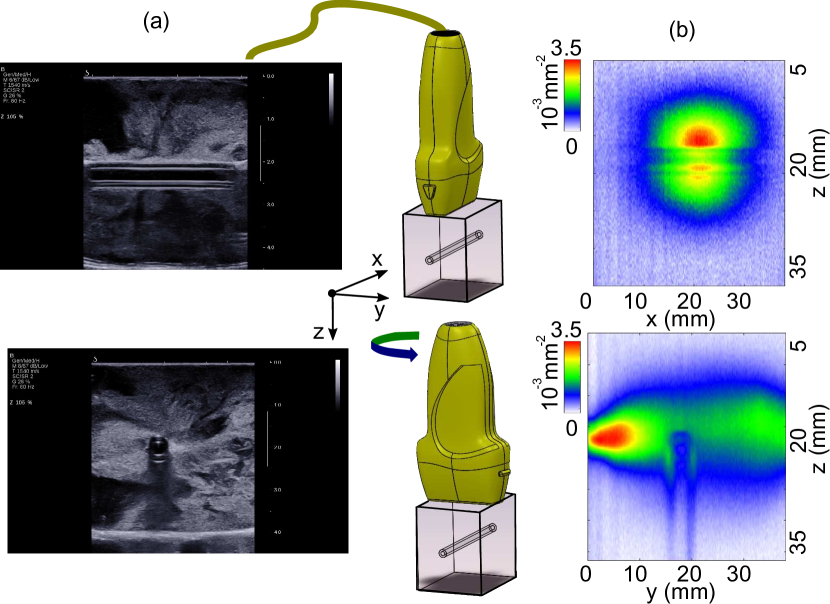

An image was then acquired as follow: for a given x𝑥x position, the acoustic probe generated a two-cycle focused wave centered at 3MHz3MHz3\,\mathrm{MHz} propagating along z𝑧z. A synchronized 14-bit acquisition card (Gage Digitizer) recorded the AO filtered signal. The z𝑧z coordinate was obtained by multiplying the acquisition time by the sound propagation in water Vus1450m/ssimilar-tosubscript𝑉𝑢𝑠1450msV_{us}\sim 1450\mathrm{m/s}. This time-resolved focusing scan along dimension x𝑥x was repeated 100010001000 times to improve signal to noise ratio through averaging. In Fig 2(b), we show the qualitative comparison between the AO image obtained when the probe is respectively orthogonal (top) and along the optical axis (bottom) . In both cases, the AO image is compared with that provided by a clinical ultrasound imaging device (Aixplorer,Supersonic Imaging) in the same respective configurations. The resulting B-mode images shown in Fig 2(a) provide only structural information on the phantom. We used them to precisely locate the tube edges in the AO image and therefore define the ROI corresponding to its inner volume. To conduct the experiment presented here, we picked the configuration where the probe is orthogonal to the optical axis (y), thereby choosing a larger tube’s ROI to minimize the signal to noise ratio after integration. The tube ROI was defined by 18.9mmz22.5mm18.9mm𝑧22.5mm18.9\,\mathrm{mm}\leq z\leq 22.5\,\mathrm{mm}.

Refer to caption

Figure 2: (a) B-mode images of the PVA phantom obtained in clinical conditions where the acoustic probe was positioned respectively orthogonal to (top) and along (bottom) the optical axis (b) AO images in the same configurations.